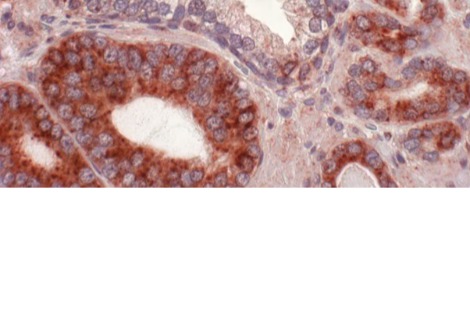

تعمل المُقترنات المشعة عن طريق توصيل نظير مشع قاتل للسرطان مع عامل استهداف يبحث عن الخلايا السرطانية ، كما كتب المحرر المساعد لي كريتش بورنر. يتكون الاتحاد من أربعة أجزاء : نظير مشع ، ومركب استهداف ، وسلة واقية للاحتفاظ بالنظير ، ورابط لتثبيت جميع الأجزاء معًا . ومع ذلك ، فإن تطوير هذه الأدوية يطرح العديد من التحديات . يجب تصميم المكونات للعمل معًا لاستهداف الورم وعدم إتلاف أجزاء أخرى من الجسم . اختيار النظائر المشعة الصحيحة هو أيضا مفتاح ؛ تركز الشركات حاليًا على نوعين من النظائر ، بواعث ألفا وبواعث بيتا ، لكل منها مزاياها وعيوبها . يمكن أن يتسبب العرض المحدود للمكونات المشعة الضرورية أيضًا في حدوث مشكلات ، حيث لا يمكن الحصول على هذه النظائر إلا من المولدات أو السيكلوترونات أو المفاعلات النووية أو النفايات المشعة القديمة .